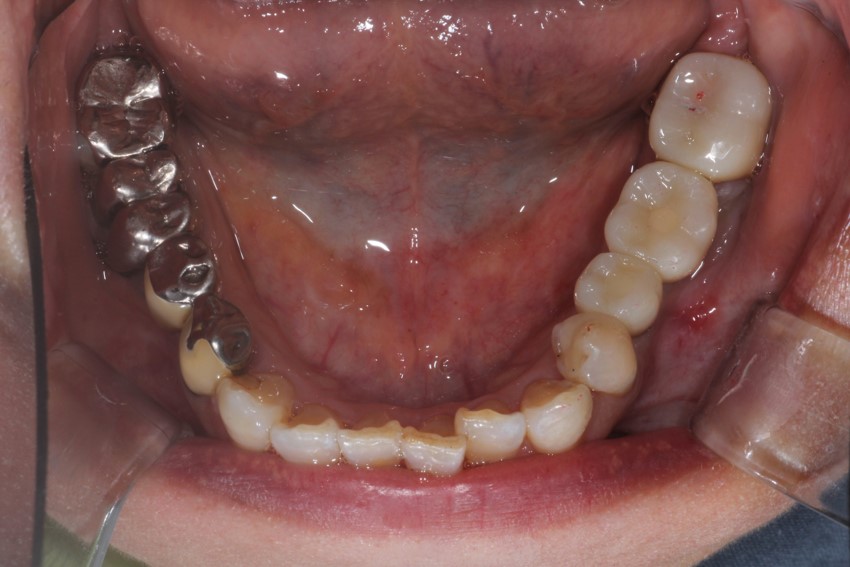

プラスチック義歯と金属義歯との違いが解りやすいように左右でその両者の材料を用いて製作してみました。

厚みが全然違うのが解ります。

お口の中で粘膜に触れる内面をみると、金属義歯の強度がプラスチック義歯とは全然違うのが見てとれます。